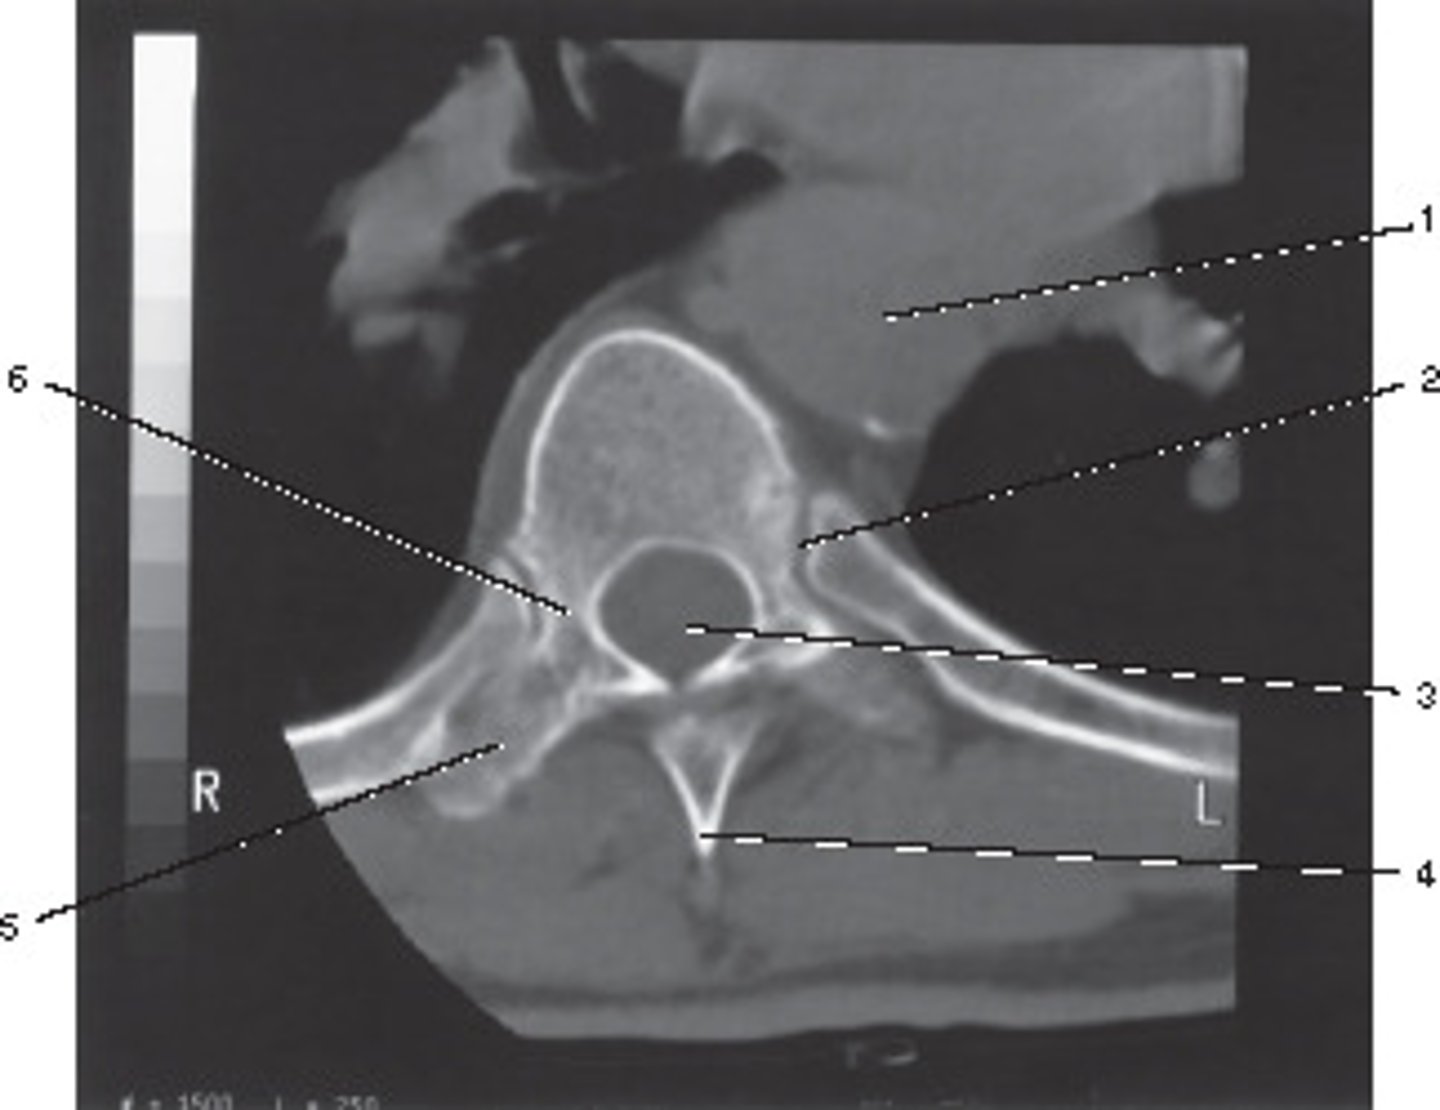

Body

Identify structure A on this axial CT slice of the lumbar vertebra.

<p>Identify structure A on this axial CT slice of the lumbar vertebra.</p>

Pedicle

Identify structure B on this axial CT slice of the lumbar vertebra.

<p>Identify structure B on this axial CT slice of the lumbar vertebra.</p>

Lamina

Identify structure C on this axial CT slice of the lumbar vertebra.

<p>Identify structure C on this axial CT slice of the lumbar vertebra.</p>

Transverse process

Identify structure D on this axial CT slice of the lumbar vertebra.

<p>Identify structure D on this axial CT slice of the lumbar vertebra.</p>

Posterior spinous process

Identify structure E on this axial CT slice of the lumbar vertebra.

<p>Identify structure E on this axial CT slice of the lumbar vertebra.</p>

Vertebral foramen

Identify structure F on this axial CT slice of the lumbar vertebra.

<p>Identify structure F on this axial CT slice of the lumbar vertebra.</p>